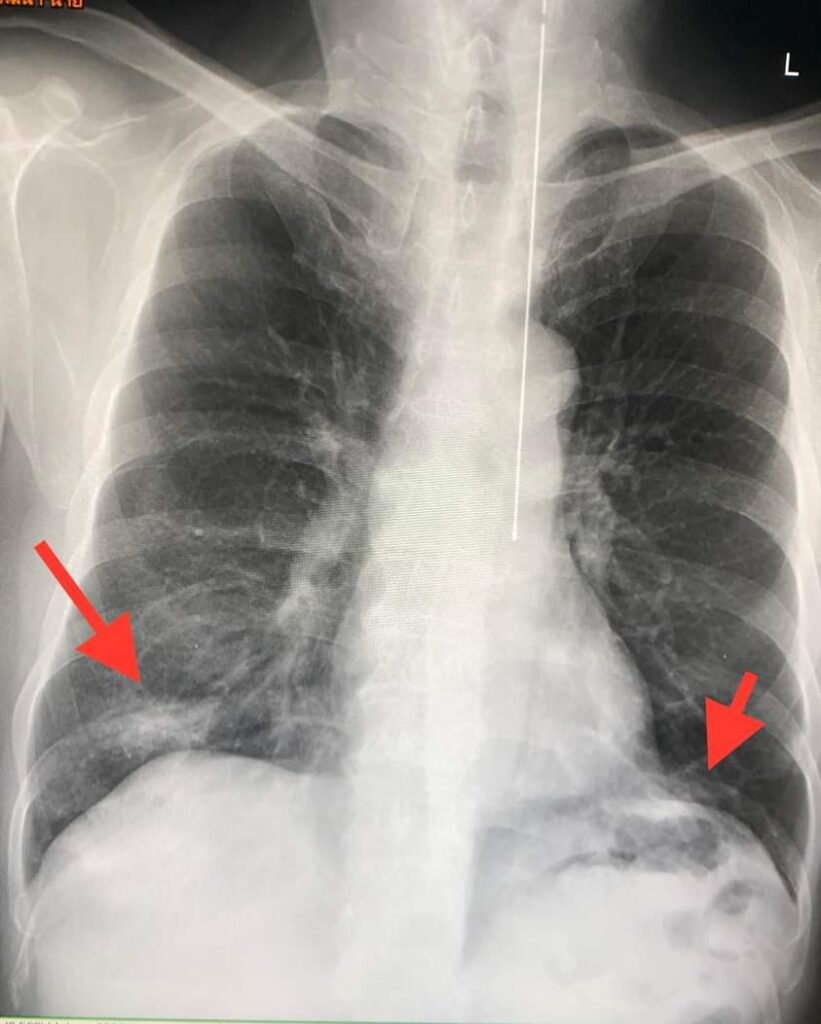

ในขณะที่ลูกชายอายุ 55 ปี อยู่บ้านเดียวกันและใกล้ชิดกับมารดา ไม่มีโรคประจำตัว ได้รับวัคซีนแอสตร้าเซเนก้าครบ 2 เข็ม ไม่มีอาการ ไม่มีไข้ ไม่ไอ จมูกได้กลิ่น ลิ้นได้รส แยงจมูกตรวจรหัสพันธุกรรม RT-PCR พบไวรัสโควิด-19 ปริมาณเชื้อมากพอๆ กับมารดา เอกซเรย์ปอดปกติ ได้ให้ยาฟาวิพิราเรียร์ (favipiravir) กิน 5 วัน หลังหยุดยา เริ่มมีไอแห้งๆ ไม่มีไข้ ไม่เหนื่อย เอกซเรย์ปอดซ้ำ มีปอดอักเสบที่ปอดด้านขวาล่างและซ้ายล่าง (ดูรูป) ติดตามอาการดีขึ้น ในที่สุดหายเป็นปกติใน 3 สัปดาห์